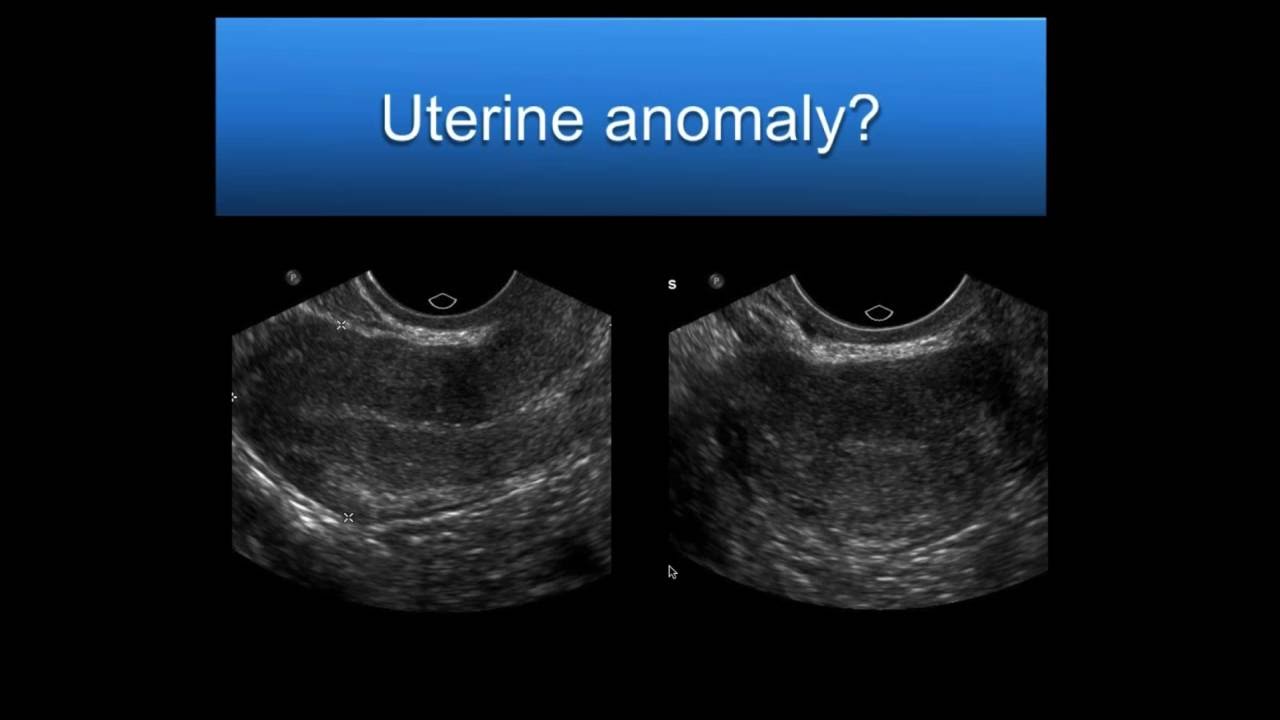

YouTube Ultrasound Ultrasound Sonography Sonography

https://i.ytimg.com/vi/zYUjp9_GHCg/maxresdefault.jpg

AIUM Webinar Problem Solving With 3D Sonography Of The Uterus And

UTERINE ULTRASOUND IMAGING